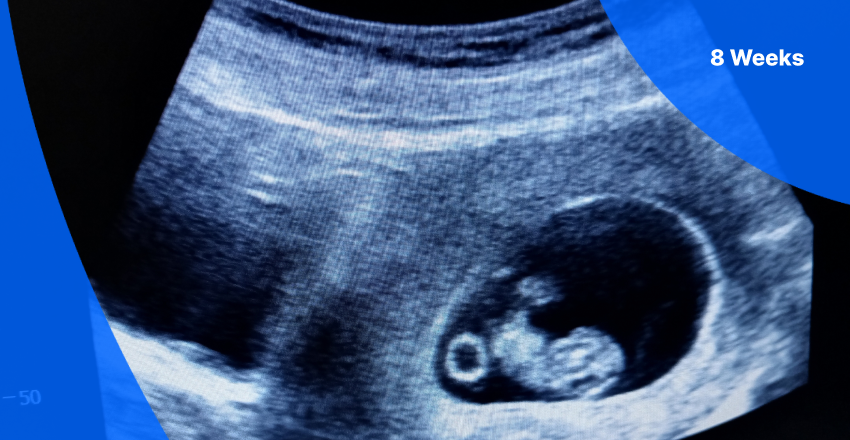

A dating scan, also called the 12-week scan, is an ultrasound scan done between 8 and 14 weeks of pregnancy. It measures the baby to help the doctor estimate how far along the pregnancy is and calculate the expected due date (EDD).

Dating Scan (6- 8 weeks)

The dating scan is usually performed between 8 and 14 weeks of pregnancy, most often between 8 and 12 weeks. At this stage, babies of the same gestational age are generally the same size, making the dating scan a reliable way to estimate the due date.